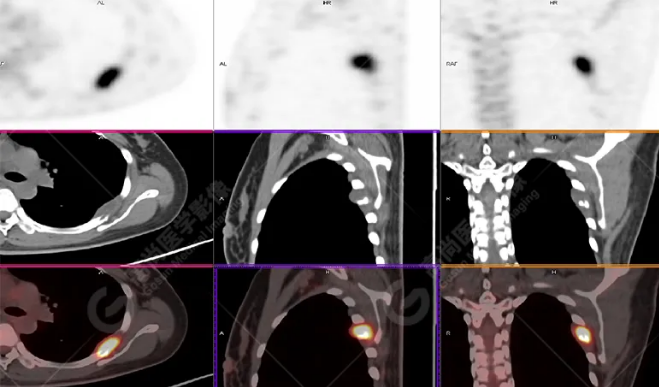

PET/CT影像圖

左胸一后肋溶骨性骨質(zhì)破壞,周?chē)檐浗M織形成,F(xiàn)DG代謝增高,SUVmax為10.9。

宮頸一片狀稍低密度影,F(xiàn)DG結(jié)節(jié)樣代謝增高,SUVmax為10.2。

最終診斷:宮頸癌伴肋骨單發(fā)骨轉(zhuǎn)移。